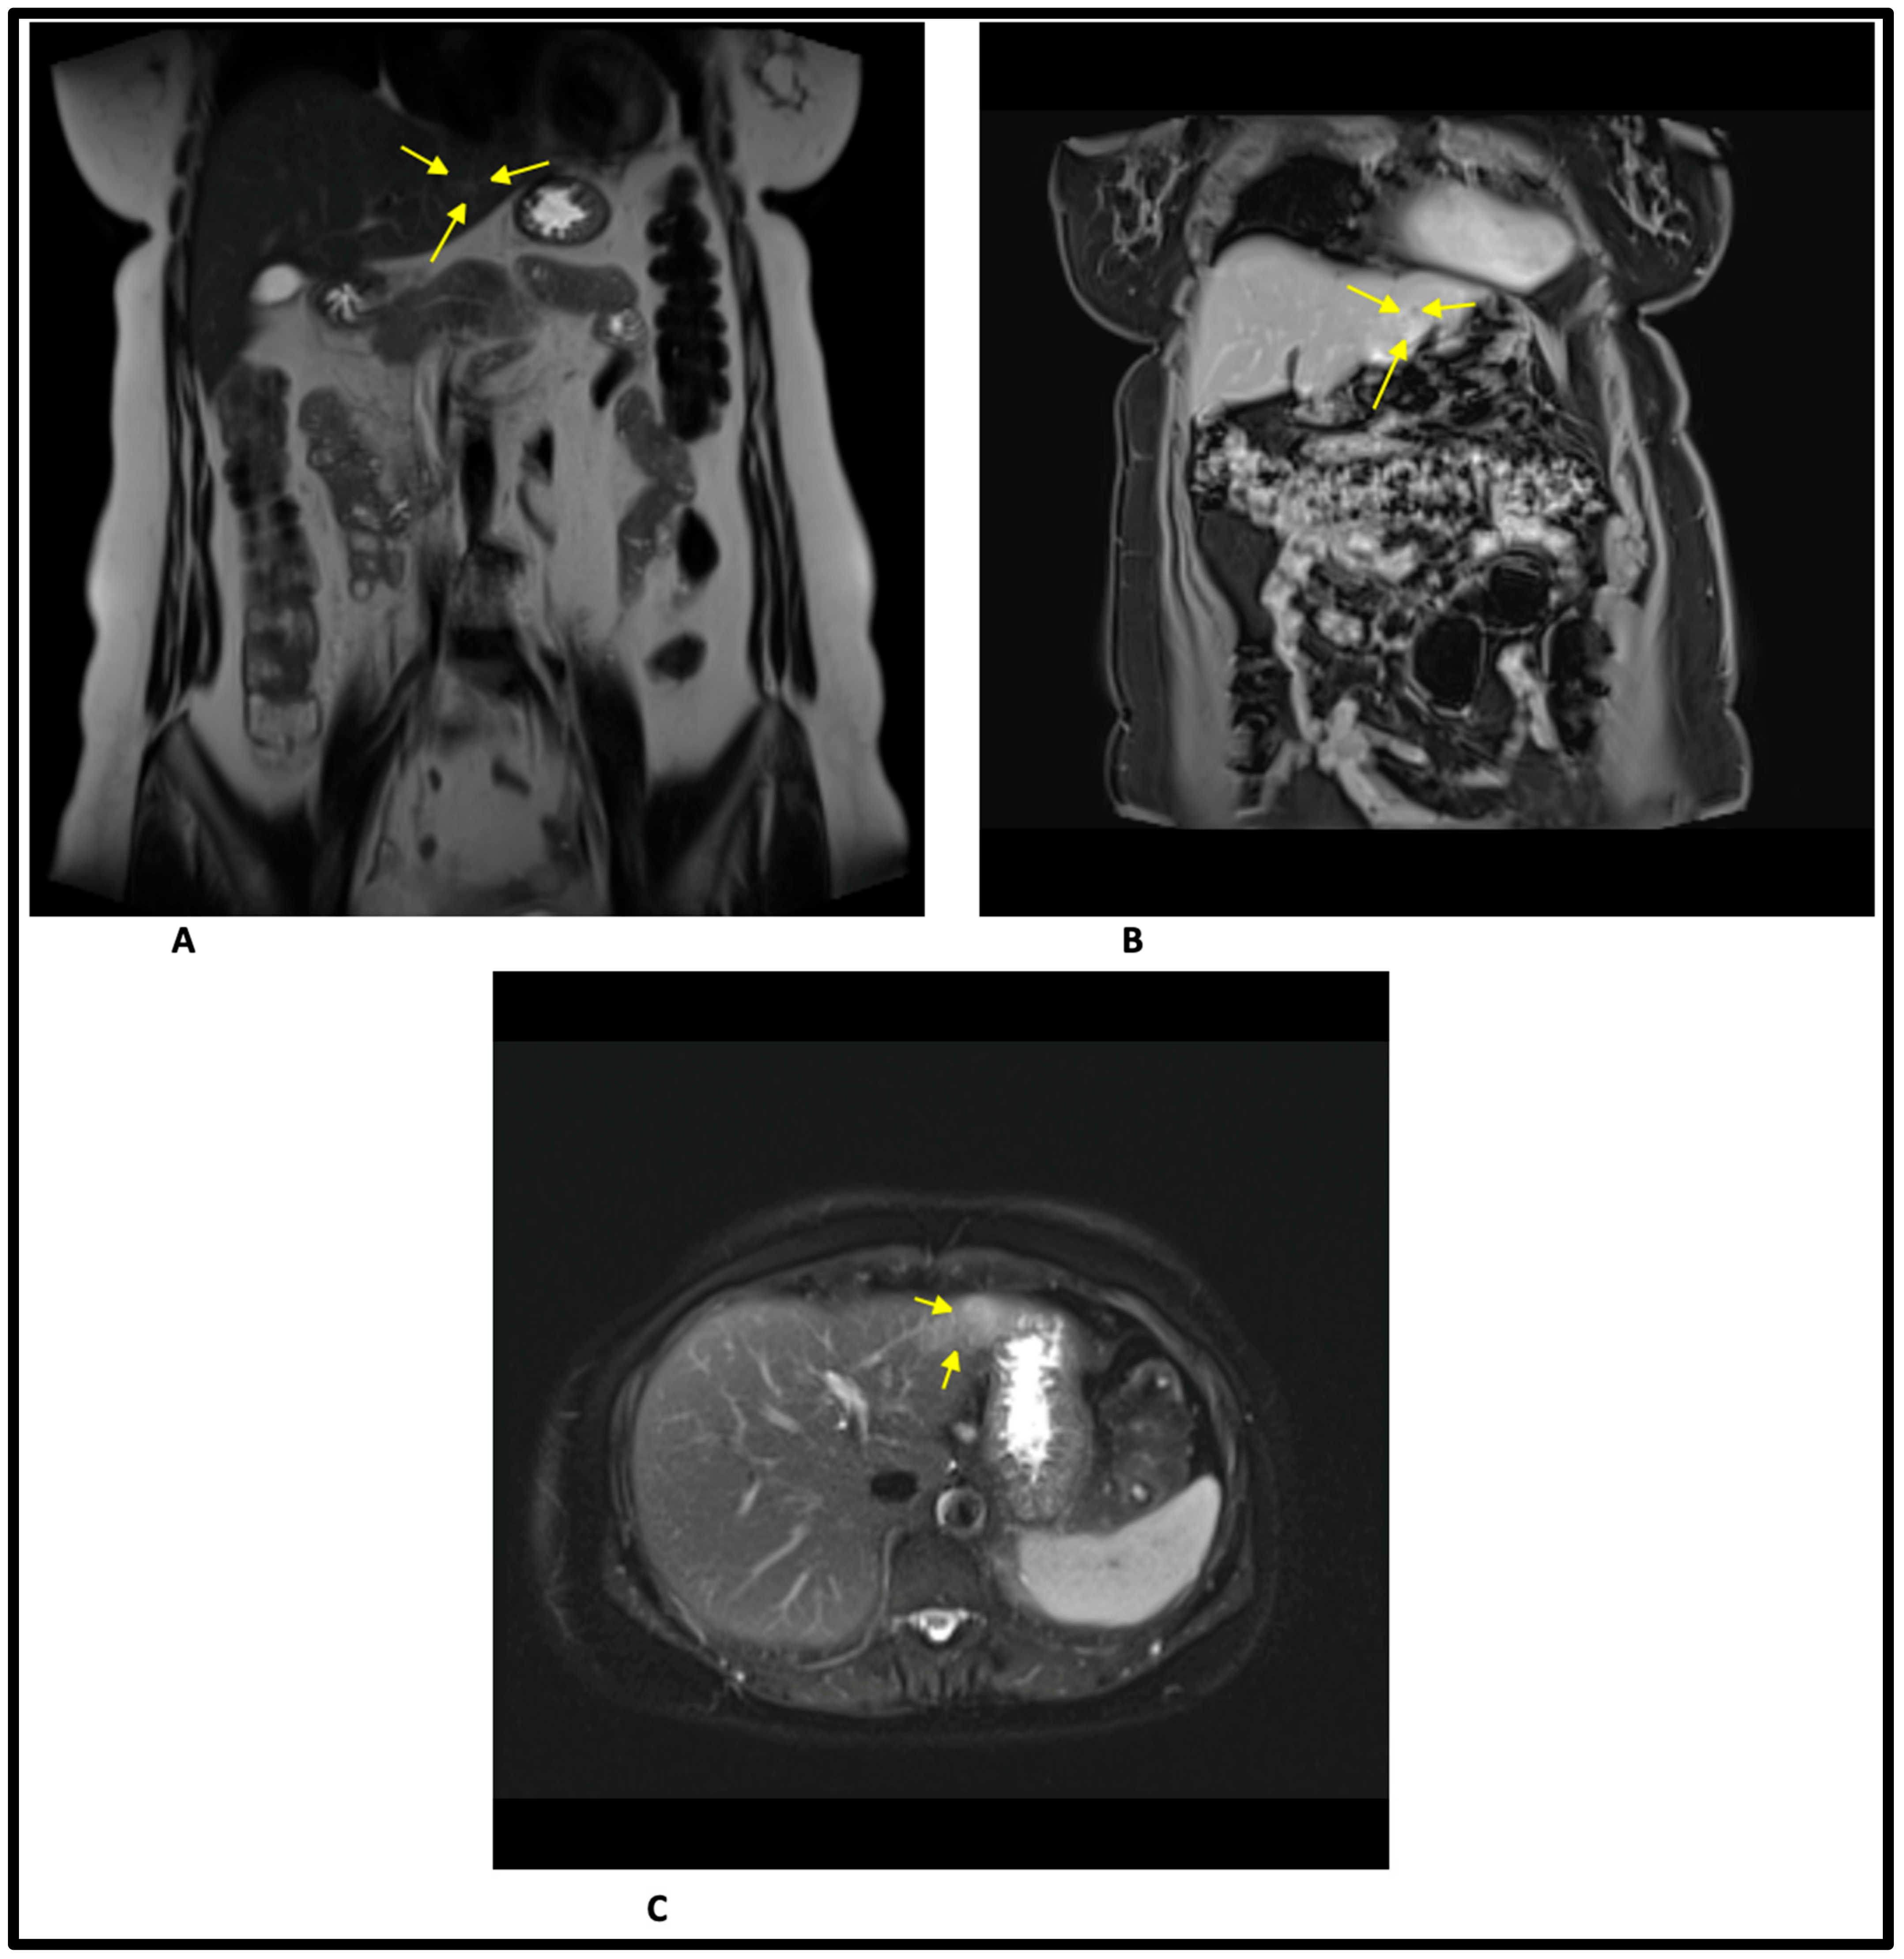

2. Case Report